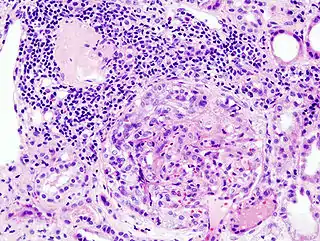

![]() Imagen histopatológica de una muestra de glomerulonefritis con semilunas obtenida de un paciente con glomerulonefritis rápidamente progresiva positiva para anticuerpos anti-MPO-ANCA. Tinción con hematoxilina y eosina. | ||

En la biopsia de estos pacientes se halla una importante proliferación de las células epiteliales de la cápsula de Bowman, con formación de semilunas en los glomérulos.[4] La biopsia renal confirma la presencia de una glomerulonefritis con semilunas epiteliales. Entre las características histopatológicas figura la infiltración del espacio urinario por células mononucleares asociada con la proliferación del epitelio parietal de la cápsula de Bowman o la proliferación extracapilar con formación de semilunas que pueden afectar del treinta al cien por ciento de los glomérulos. En estos se ve un engrosamiento de la cápsula de Bowman con formación de semilunas. También puede haber fibrosis parcial y sinequia del penacho glomerular a la cápsula.[4] Las semilunas, que pueden ser segmentarias o circunferenciales, ocupan todo el espacio de Bowman y ahogan el ovillo capilar, según el estado evolutivo pueden clasificarse en celulares, fibrocelulares o fibrosas y representan fases progresivas del mismo proceso.[4] En la glomerulonefritis rápidamente progresiva de tipo I hay positividad lineal sobre todo para IgG pero después también para C3. Dos tercios de las glomerulonefritis semilunares de este tipo corresponden al síndrome de Goodpasture y el otro tercio carece de manifestaciones pulmonares (síndrome de Goodpasture sin compromiso pulmonar). La lesión glomerular es similar en ambos grupos y se produce por un mecanismo inmunitario antimembrana basal glomerular. Como ya se dijo, el factor desencadenante es un defecto de un componente proteico de la cadena α3 del colágeno de tipo IV.[5] En la enfermedad de tipo II hay positividad granular o nodular o de ambas formas, difusa y global, debido a depósitos de complejos inmunes que con el microscopio electrónico se ven como depósitos densos. Este tipo por lo general corresponde a variedades de la glomerulonefritis aguda difusa, de la glomerulonefritis mesangiocapilar y, menos a menudo, de la enfermedad de Berger.[5]

Por último, en la glomerulonefritis semilunar de tipo III el examen con inmunofluorescencia es negativo y los hallazgos detectados con el microscopio electrónico son similares a los de la enfermedad de tipo I (sin depósitos densos). Si bien se ignora la patogenia de esta lesión glomerular, se piensa que en una buena cantidad de casos la causa de la ruptura de capilares glomerulares y de la proliferación celular glomérulo-capsular sería una vasculitis o una angiopatía. Este cuadro se observa con mayor frecuencia en adultos mayores.[5]